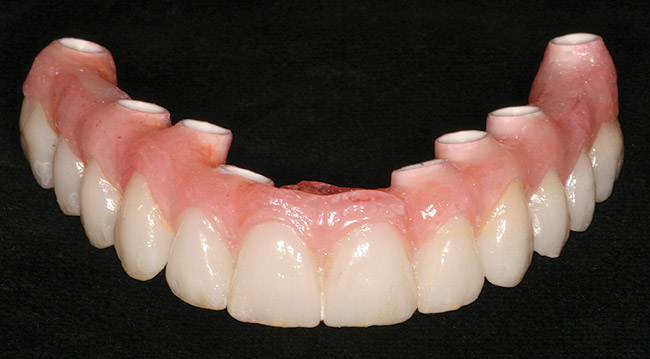

Figure 16  Laboratory-processed provisional restoration fabricated prior to surgery.

Figure 16